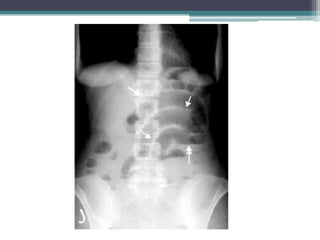

Tài liệu bàn về tắc ruột, bao gồm định nghĩa, phân loại và nguyên nhân của tình trạng này, với sự phân biệt giữa tắc cơ học và cơ năng. Các triệu chứng và chẩn đoán lâm sàng được trình bày, kèm theo phương pháp chẩn đoán cận lâm sàng như x-quang và siêu âm. Ngoài ra, tài liệu cũng đề cập đến các biến chứng và hậu quả của tắc ruột.